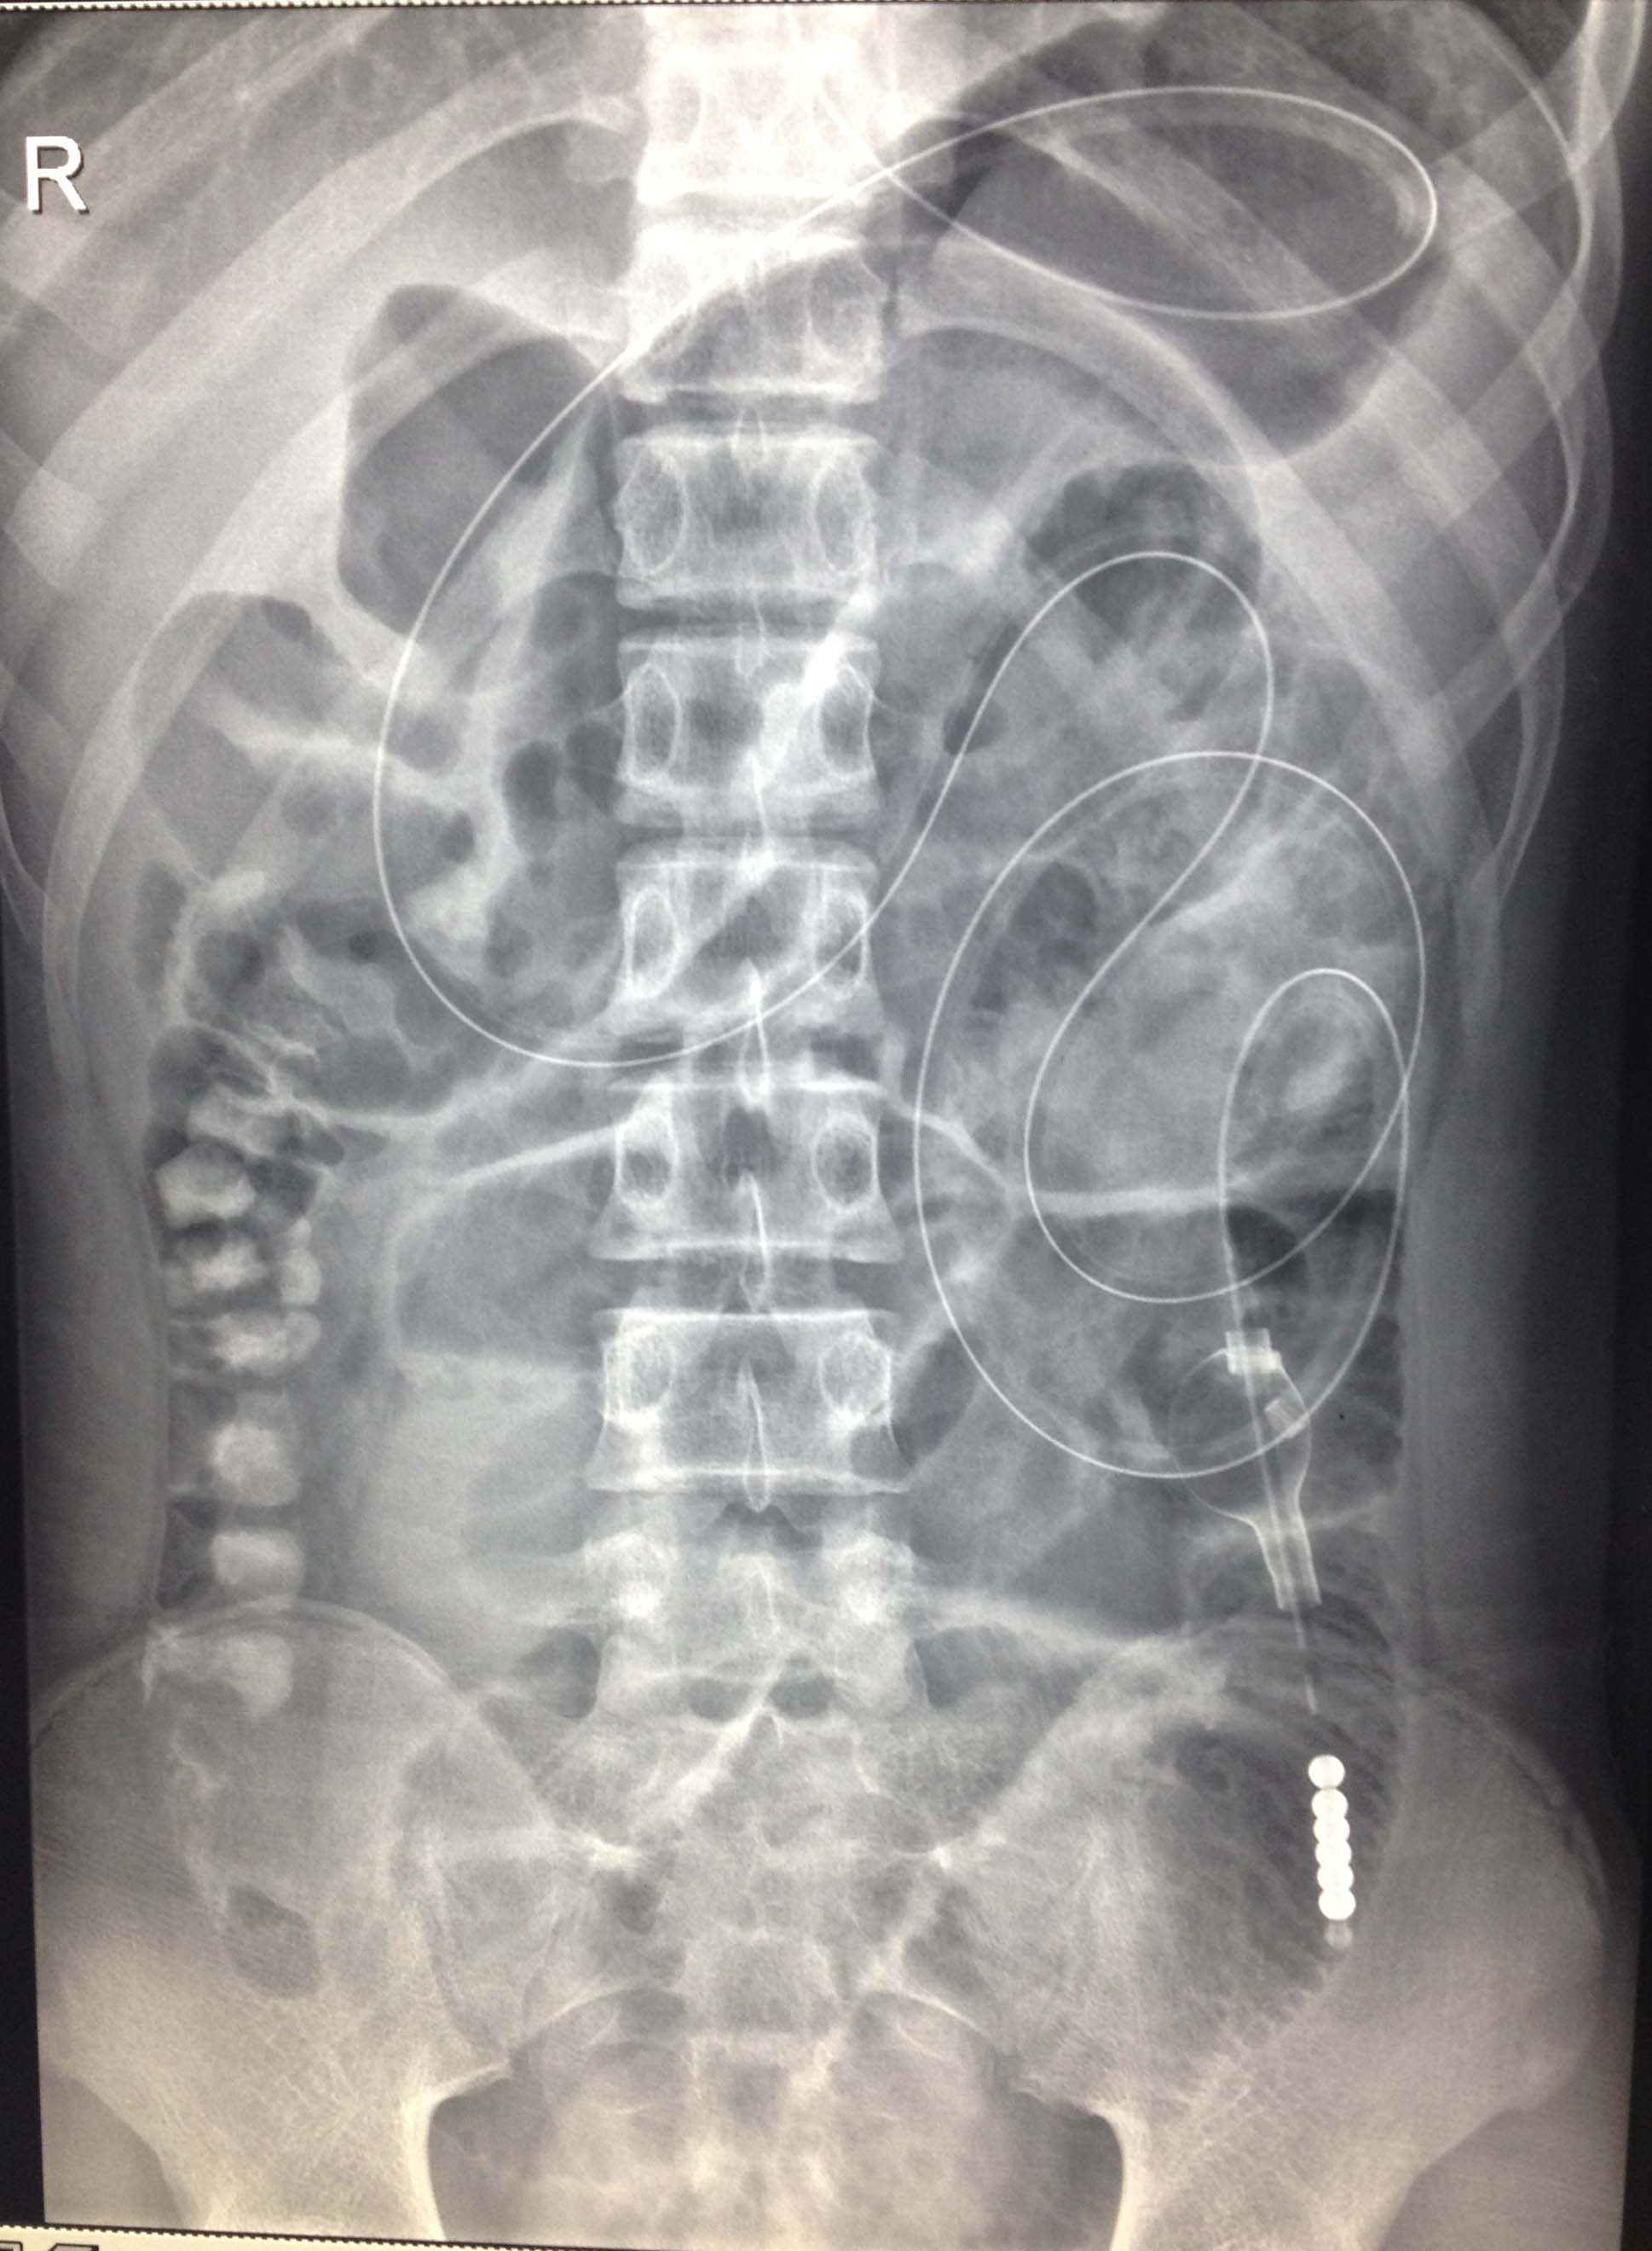

入院时腹部平片提示肠梗阻